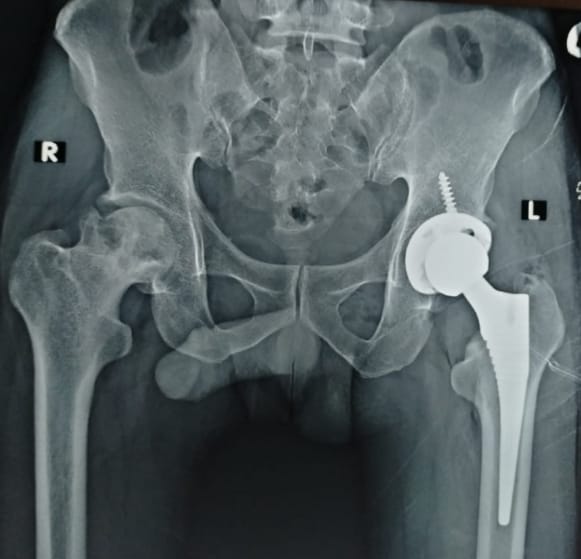

Total Hip Replacement using DAA (Minimally Invasive)

HIP